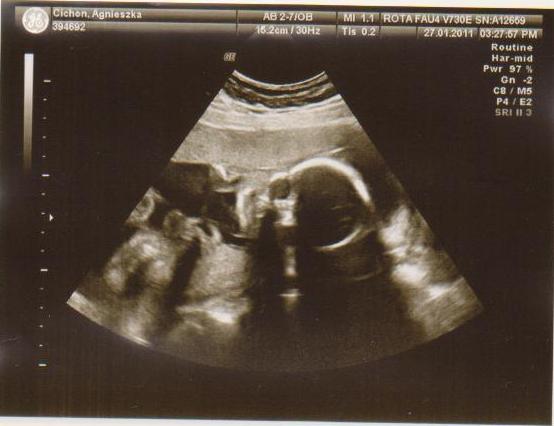

cześć dziewczyny to i ja chciałabym do Was dołączyć, właśnie znalazłam to forum. Mieszkam w Irlandii od 4 lat i mam synka 21 miesięcy, a teraz jestem w 28 tc bliźniaczej :-) dwie dziewczynki dwujajowe :-) też mnie trochę przeraża poród bliźniaków ale trzeba jakoś urodzić ;-) Pierwszy poród miałam jak marzenie szybko, sprawnie i nawet bez znieczulenia, mam nadzieję że i tym razem bęzie podobnie.

Hej podwojne mamunie:-)Ja juz rozpakowana dawno mamusia dubeltowka.Gratuluje wam serdecznie i witam w gronie tych wybranych hihiNiczego sie nie bojcie.Ciaxa blizniacza jest pod specjalna opieka.Czekaja was czeste wizyty w szpitalu i czeste ogladanie maluszkow na usg :-)